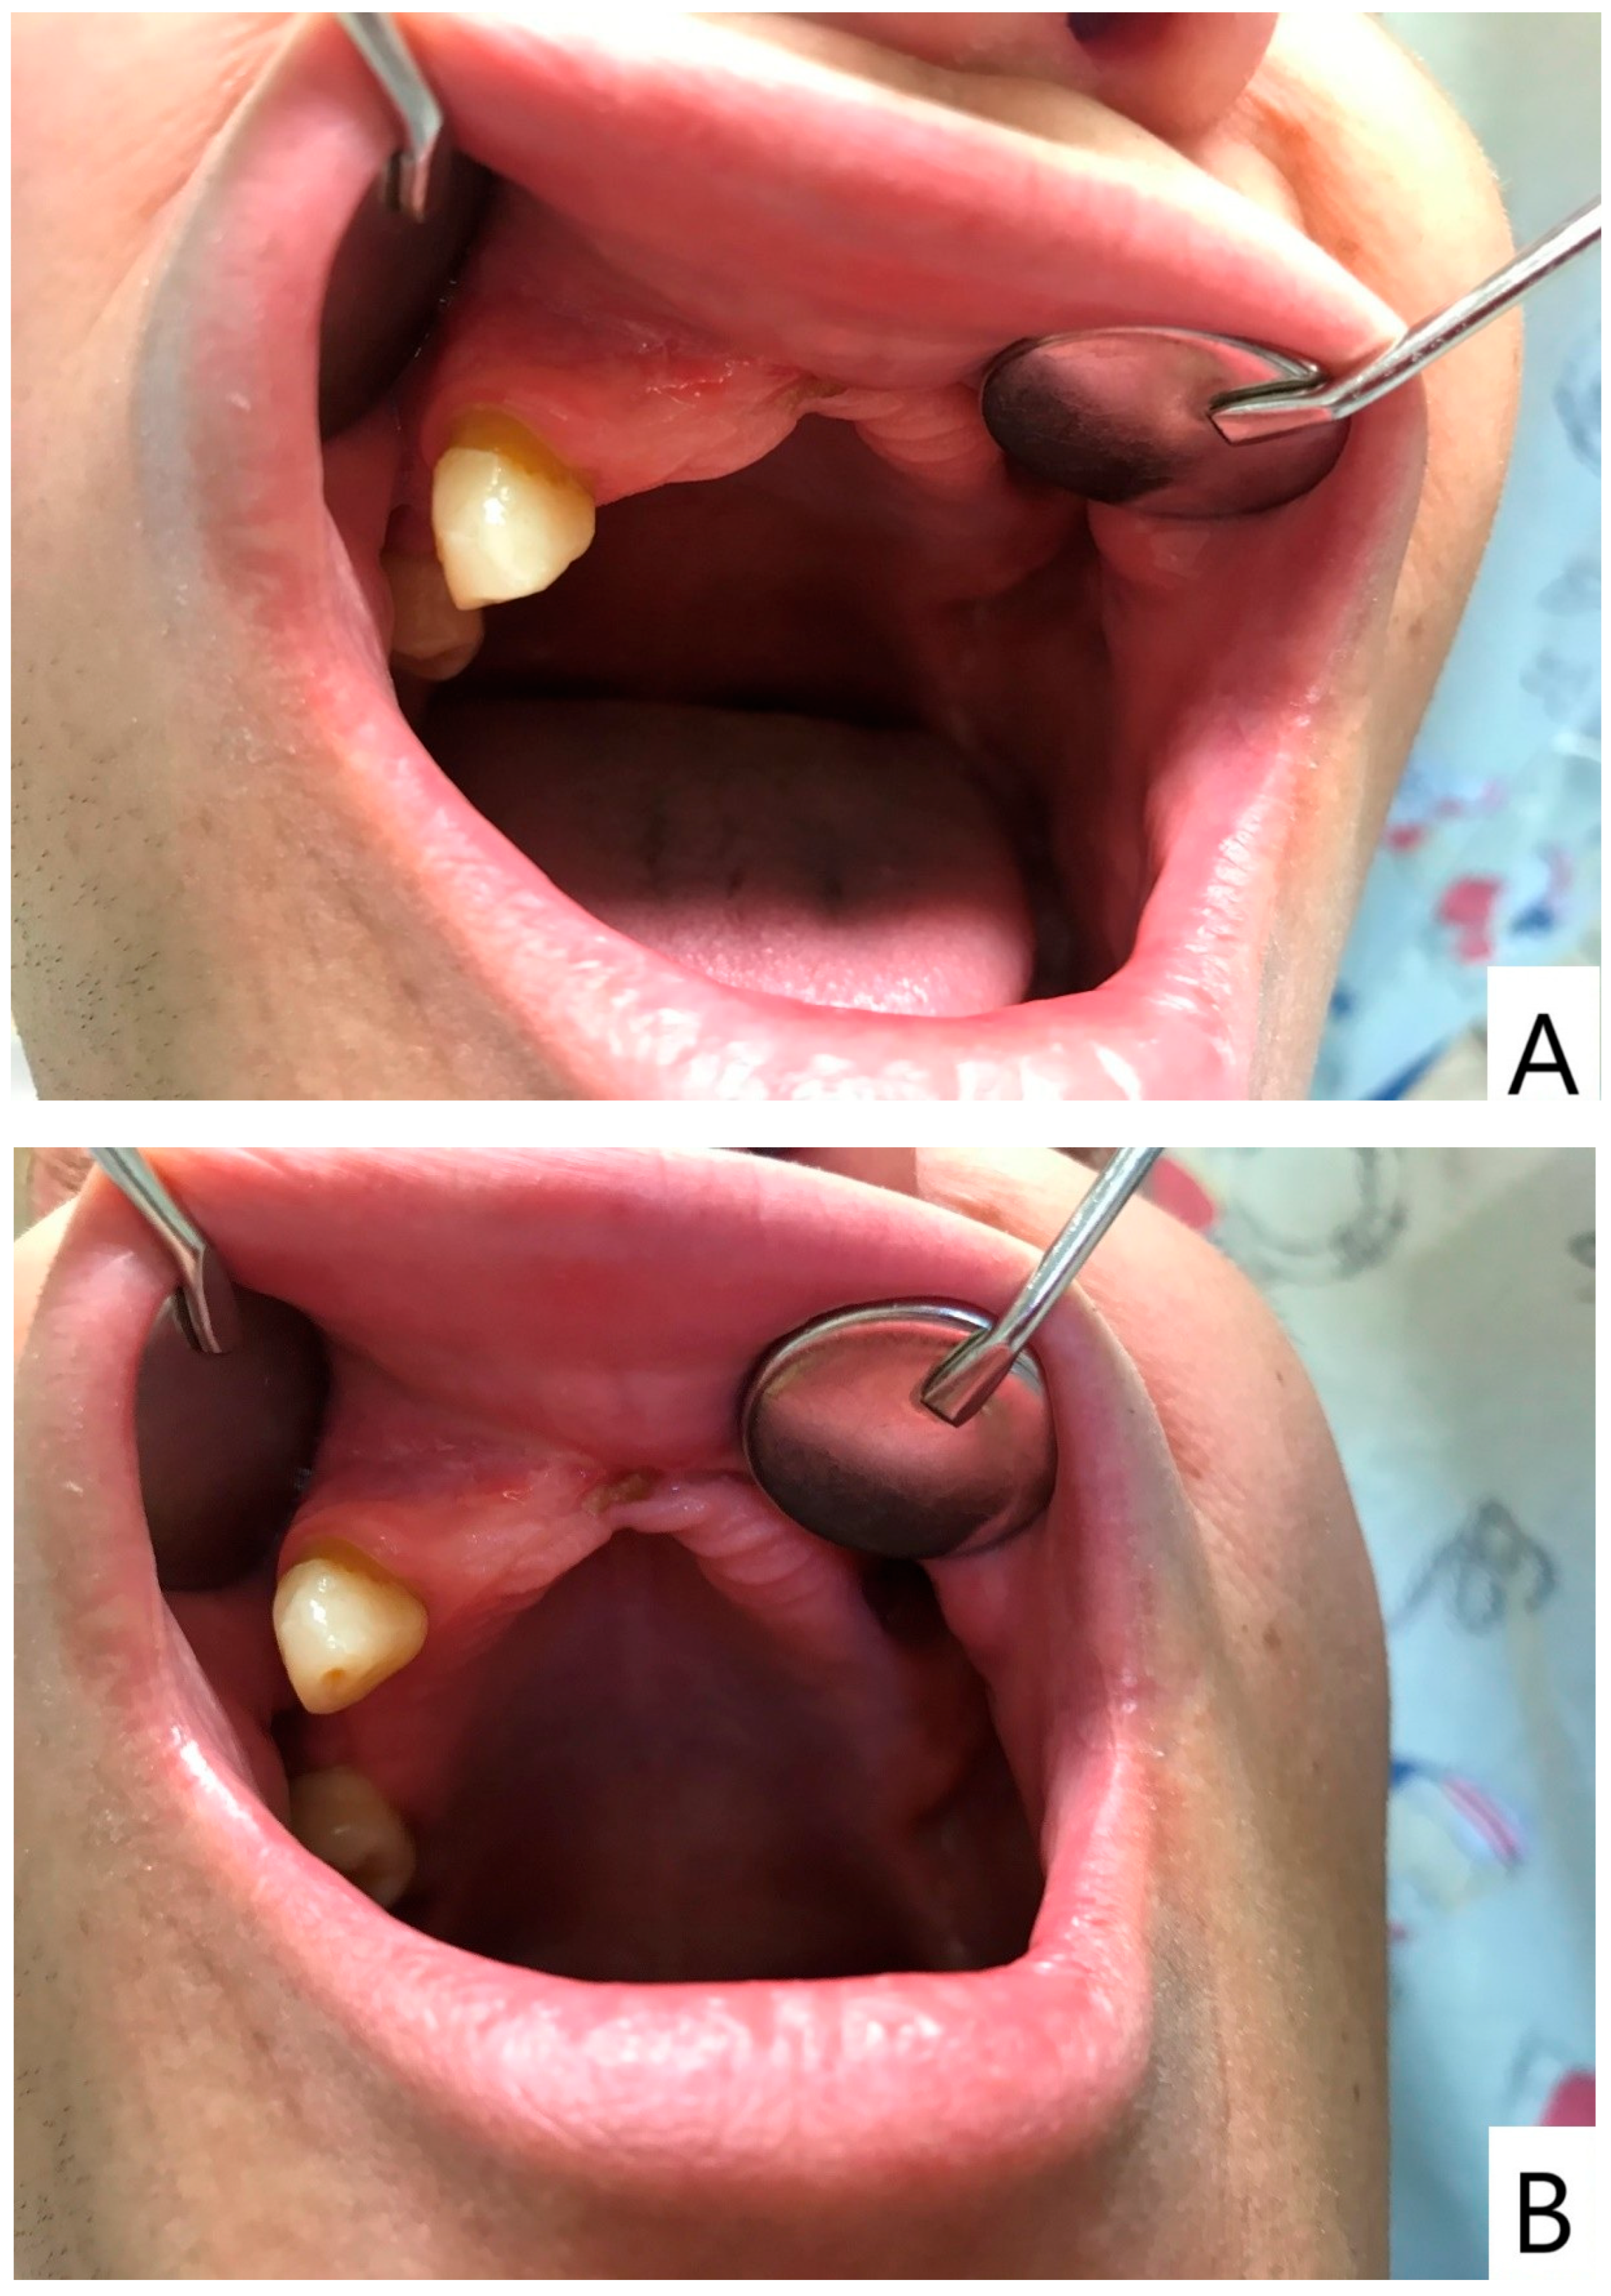

Following a minor facial trauma, the patient developed nonspecific symptoms, including left midfacial discomfort, subjective nasal obstruction in the absence of sinonasal involvement, and dull facial pain. At the time of his first presentation to our clinic, the oral mucosa already showed advanced pathological changes. Physical and radiological examinations did not reveal traumatic injuries or findings that could adequately explain the severity of the clinical presentation (Figure 1 and Figure 2).

Intraoral examination at initial evaluation revealed an ulcerative, bleeding palatal lesion covered by pseudomembranous exudate, accompanied by surrounding inflammation. Additional findings included multiple root remnants, extensive carious lesions, periostitis, and severe dental neglect (Figure 1). Despite targeted ambulatory antibiotic therapy, antifungal treatment (fluconazole 100 mg twice daily), and local dental interventions, the lesion failed to regress and demonstrated further progression, with increasing tissue destruction involving the palate, left maxillary process, and adjacent gingival tissues. Periodontal swelling and pathological mobility of the maxillary teeth were also observed.

Figure 1. (A) Overview of the oral cavity demonstrating severe dental neglect and inflammatory changes. (B) Close-up view of the left palatal region showing a destructive ulcerative lesion with irregular margins, pseudomembranous covering, and hemorrhagic surface, representing the primary manifestation of extranodal NK/T-cell lymphoma in this case. Please note that several severely compromised maxillary teeth visible on the initial panoramic radiograph were extracted during acute dental management prior to photographic documentation; therefore, the intraoral images reflect the clinical status after initial emergency interventions.

Figure 5. Oral manifestation of ENKTCL following clinical remission. (A) Intraoral view demonstrating marked regression of the previously ulcerative palatal lesion after completion of combined oncologic and supportive dental management. (B) Additional intraoral photograph obtained at the same follow-up visit from a different angle, confirming mucosal healing and absence of active ulceration.